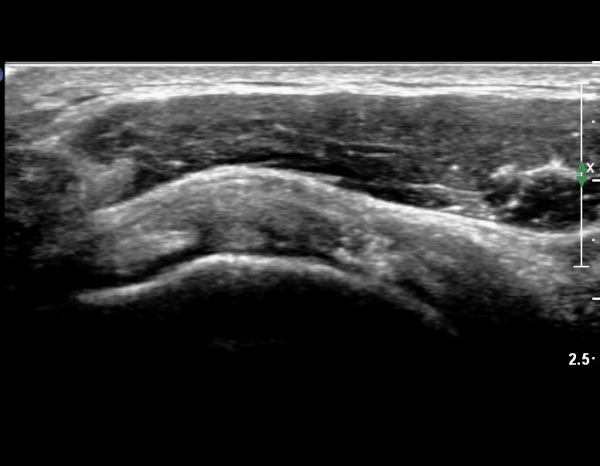

°ß°©ÇÏ±Ù°Ç Á¾´Ü¸ç°Ë»ç¿¡¼­ °Ç »óºÎ¿¡ ÀÌÁúÀûÀÎ ¿¡ÄÚ¸¦ º¸¿© °ß°©ÇÏ±Ù°Ç »óºÎ ºÎºÐÆÄ¿­ÀÌ ÃßÁ¤µÈ´Ù(»çÁø 3),

°ß°©ÇÏ±Ù°Ç ÇϺο¡¼­´Â ÀÌ»ó ¼Ò°ßÀÌ °üÂûµÇÁö ¾Ê´Â´Ù(»çÁø 4).